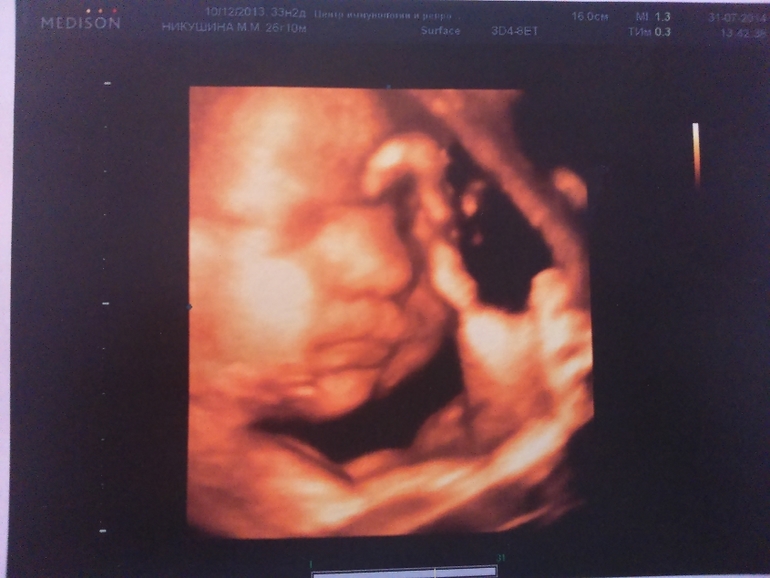

Лежит наш слоненок головой вниз, прижавшись к стенке матки носом, поэтому 3Д фотографии личика не очень вышли хорошо. зато причиндалы демонстрировал охотно)))

А сам сыночек такой классный)) хмурился, жмурился, плевался)) стопа уже 7 см

ну и пара фоточек (не очень лицо видно было, но разглядели папины щеки и губы и мой нос))))